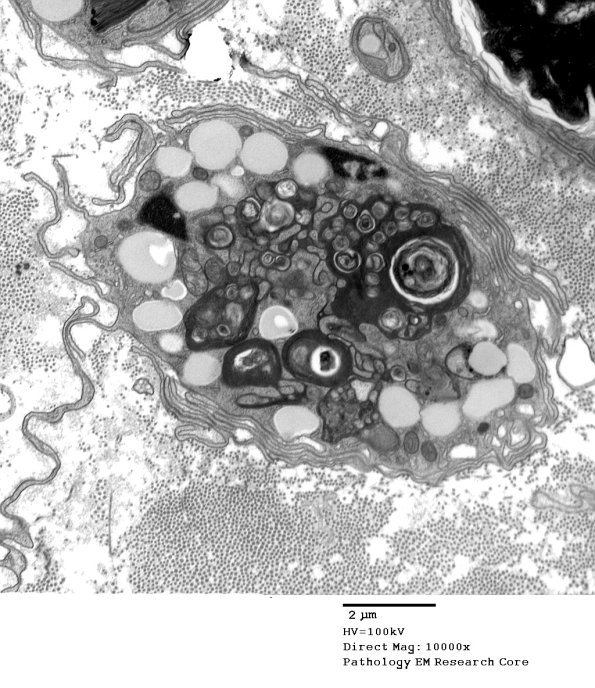

4E1,2 A migrating macrophage containing partially metabolized myelin and axonal debris.